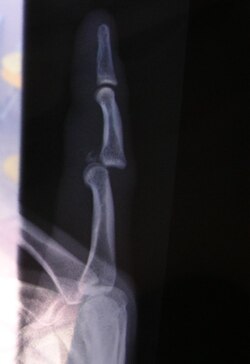

Iščašenje, česta ozljeda na radnom mjestu